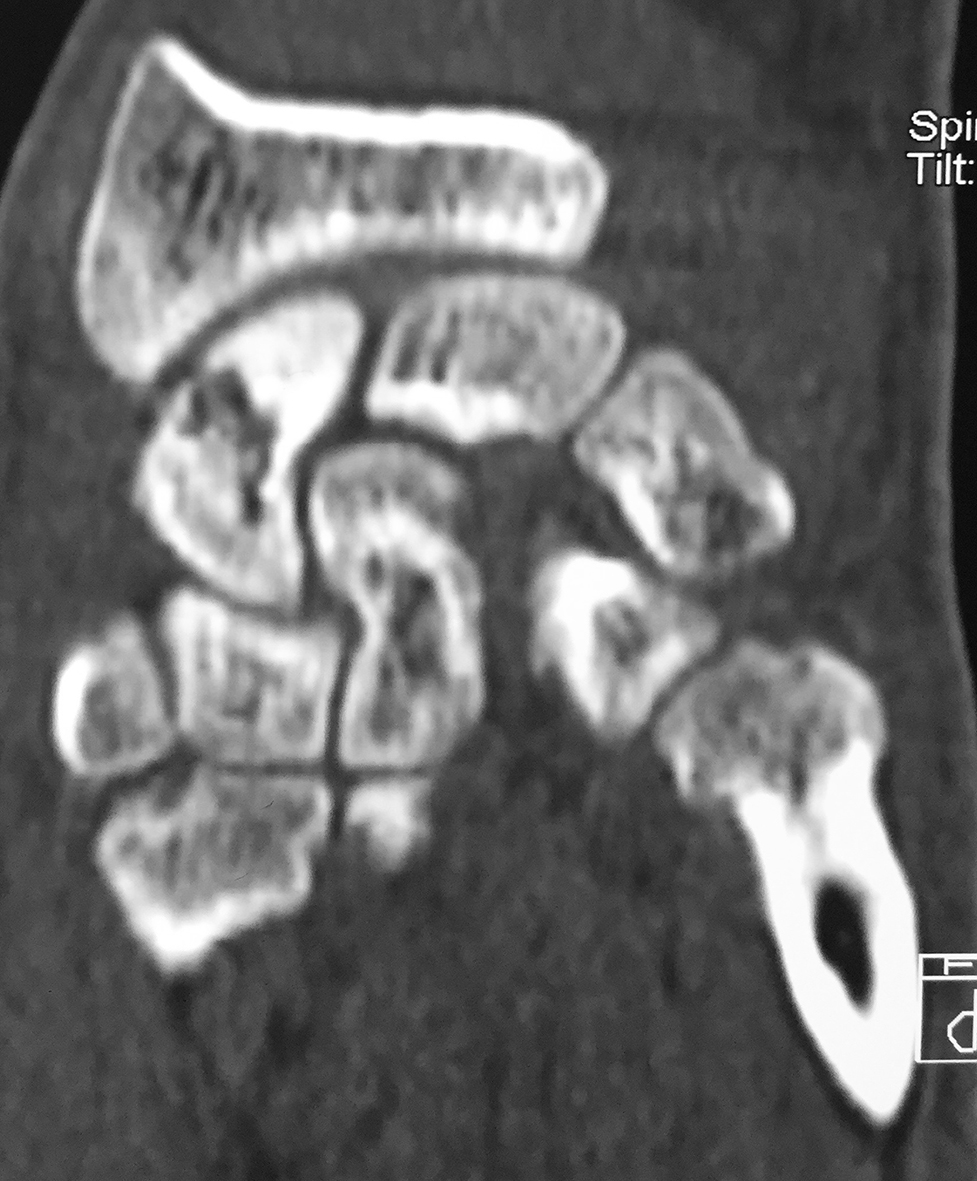

Figura 3: Caso 9

a) Radiografia de perfil pre-opertaoria

b) TC pre-operatoria. Corte sagital

c) TC pre-operatoria. Corte coronal

d) Radiografías post-operatorias

e) Radiografía de frente, 33 meses seguimiento, pseuodartrosis persistente

f) Radiografía de frente, 33 meses seguimiento, pseuodartrosis persistente